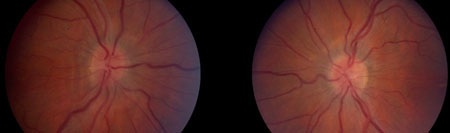

Idiopathic intracranial hypertension

Bilateral optic atrophy

From the personal collection of Dr M. Wall; used with permission